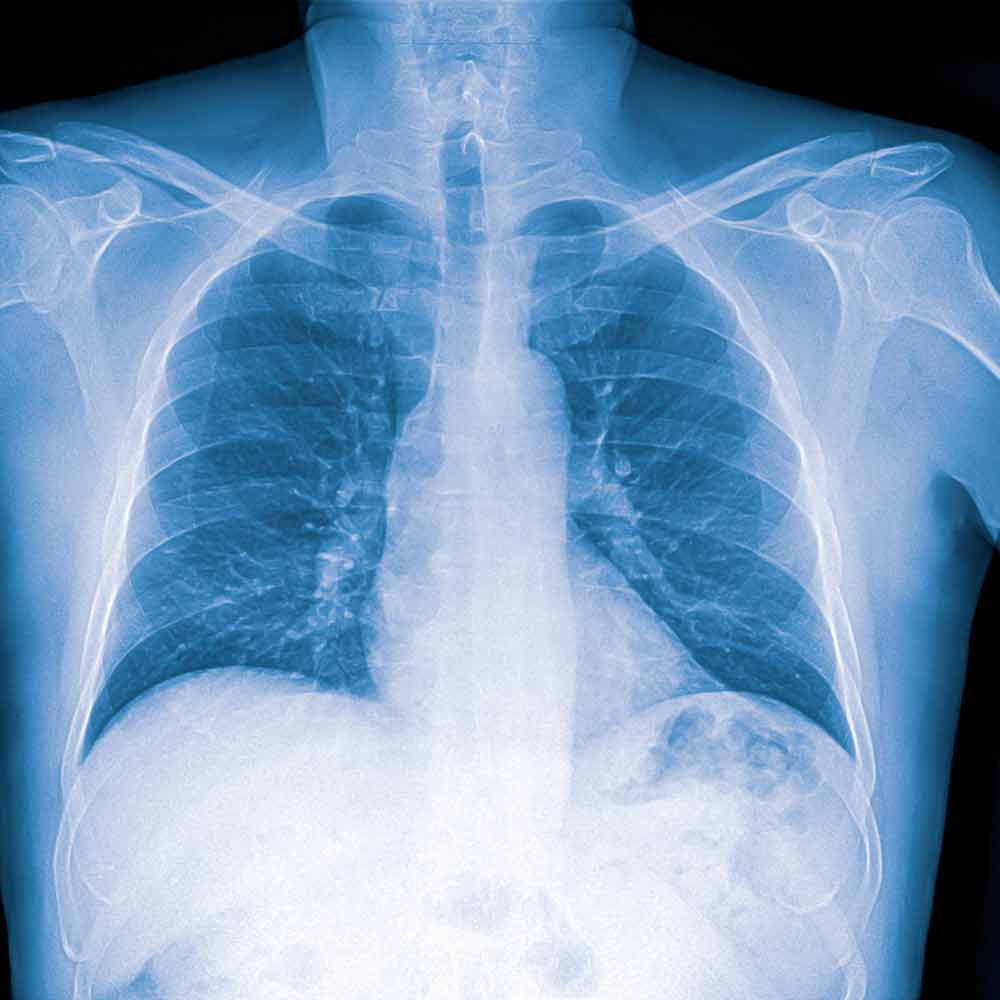

Legen starter med en klinisk undersøkelse, der det blant annet lyttes på lungene med stetoskop for å høre etter knatrelyder eller redusert pustelyd. I tillegg tas ofte en blodprøve (CRP), som kan gi en pekepinn på om infeksjonen er bakteriell eller viral – høye verdier taler ofte for bakterieinfeksjon. Dersom diagnosen er usikker, eller hvis pasienten er i en risikogruppe, kan det være aktuelt med røntgen av lungene for å bekrefte lungebetennelsen.

Lungebetennelse kan ses som et hvitt område på røntgenbilde av lungene.